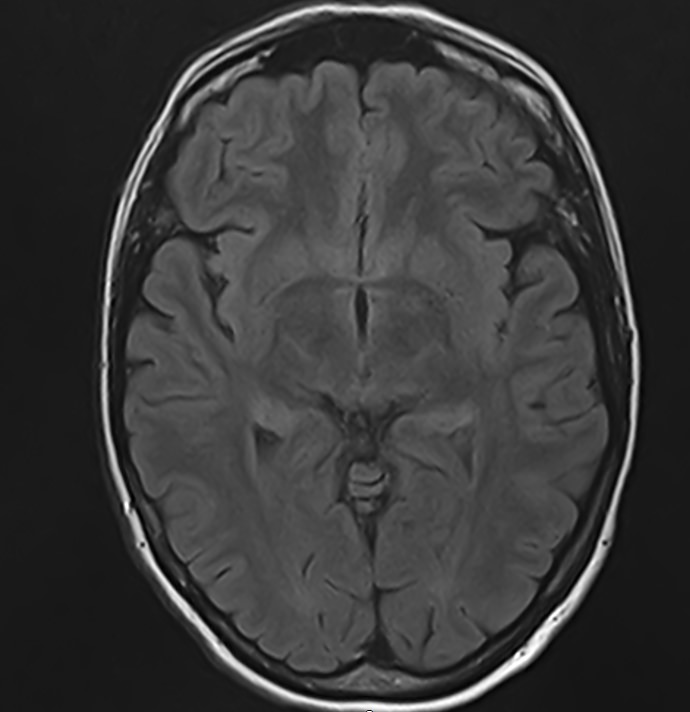

Стандартная МРТ головного мозга дает важную информацию о состоянии и структуре мозговой ткани для выявления большого числа заболеваний, в том числе опухолевых образований, демиелинизирующих заболеваний, воспалительных процессов головного мозга и мозговых оболочек. Стандартную МРТ головного мозга дополняет МР-ангиография, которая отображает состояние системы кровоснабжения головы и шеи. Компьютерная программа обрабатывает данные, полученные при сканировании, и формирует объемные изображения как самого мозга, так и сосудистой системы в отдельности без прилегающих тканей. Обе методики применяются одновременно и взаимодополняют друг друга, давая полную диагностическую картину.

Исследование предоставляет информацию о состоянии тканей головного мозга и оболочек, проходимости кровеносных сосудов, наличии и размерах опухолей, тромбов, гематом и других патологий. Изучив изображения, нейрохирург или другой специалист получает информацию о локализации патологии, степени повреждения тканей мозга, может принять решение о проведении операции либо контролировать ход лечения.